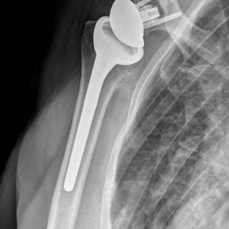

Seine Langzeit-Nachuntersuchung zur Haltbarkeit und Funktion von inversen Schulterprothesen erschien jetzt im Journal of Shoulder and Elbow Surgery – ein Ritterschlag, handelt es sich doch um das weltweit bekannteste und hochwertigste Fachjournal für Schulterchirurgie.

Gute Nachricht für Patienten: Im Artikel wird gezeigt, dass inverse Prothesen auch bei schwierigen Fällen und nach Wechseloperationen besser abschneiden, als bisher erwartet.